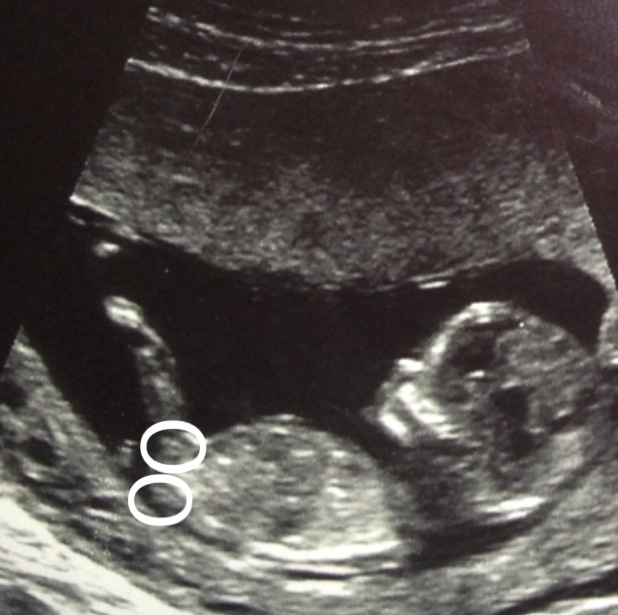

This us my second scan photo not showing a clear nub, i gave circled what i think iir could be most probably the top one but over all what do you feel? Pink or blue?

Bottom circle is spine and top circle may show part of the nub but not enough to give an accurate guess on.

if that is the nub in top circle its a boy